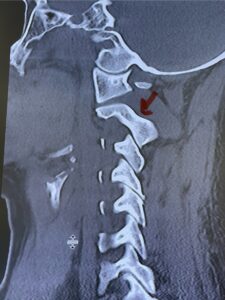

Cervical x-rays revealed a significantly increased atlanto-axial interval (Fig. 5) On review of her imaging studies it was noted that the right C2 isthmus was very thinned by the vertebral foramen (Figs 6a, b, and c) which would make an attempt at placing a C2 pars screw dangerous. A decision was made to perform an occipital-cervical fusion because only possible unilateral fixation and an extensive C1 laminectomy to be performed eliminating a fixation point if a more traditional C1-C2 was performed. Even if C1 lateral mass screws were able to be placed one could only perform a unilateral screw construct fixation to C2. We performed an occipital cervical fusion down to C4 to get enough inferior fixation and C1 laminectomy. The decompression went well. We placed a left unilateral pars screw and bilateral C3 and C4 lateral mass screws. We placed three 12 mm screws in the midline keel (Fig. 7). Postoperatively the patient had all around improvement in her symptoms and did not qualify for rehab. Her post op films at 6 weeks (Fig. 8)

Fig. 6a: Sagittal cervical CT scan demonstrating an abnormally thin right C2 isthmus prohibiting safe placement of screw (red arrow). Notice the vertebral foramen eroding the isthmus bone structure (red dot).

Fig. 6b: Sagittal cervical CT scan demonstrating normal thickness of the left C2 isthmus (red arrow)

Fig. 6c: Axial cervical CT scan demonstrating a very thin right C2 isthmus (red arrow) compared to left side.